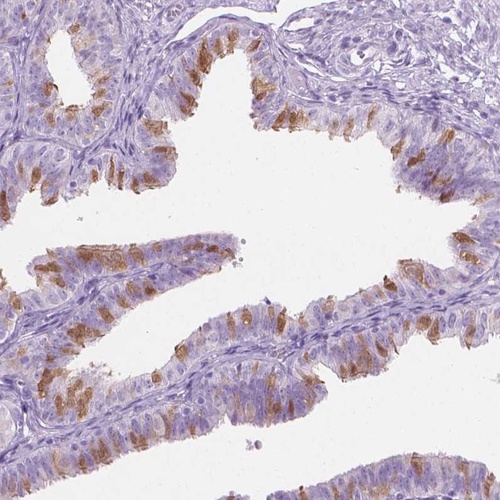

Immunohistochemical staining of human fallopian tube shows positivity in cilia and ciliated cells.